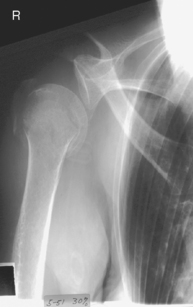

AP trauma projection (neutral rotation) (S)

Important for humerus and shoulder projections: Do not attempt to rotate upper limb if fracture or dislocation is suspected without special orders by a physician.

Warning: Do not attempt if fracture or dislocation is suspected.